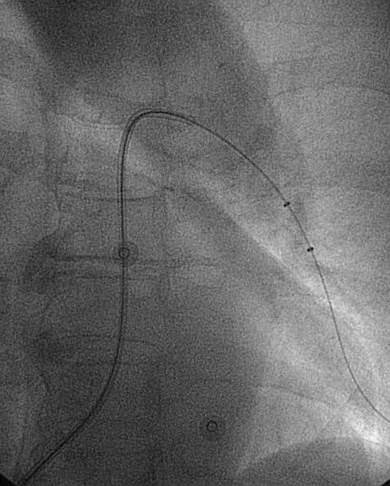

Angiografía de la arteria pulmonar izquierda realizada con un catéter en espiral de 6 F en ángulo, que demuestra la presencia de un trombo dentro de la arteria pulmonar izquierda y en las bifurcaciones lobulares intermedia, inferior y superior.

Se efectuó una trombectomía reolítica con el catéter PE de AngioJet® mediante un catéter guía multifunción de 8 F y una guía de angioplastia hidrófila de 0,035’’.

Angiografía pulmonar izquierda realizada tras una trombectomía reolítica en la que se muestra la mejora del índice de perfusión y obstrucción.